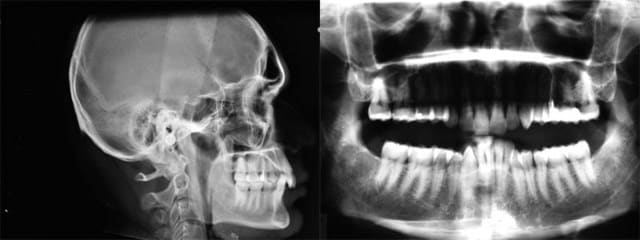

je t’envoie les Rx. avant

Rx.

Rx - Eugenol